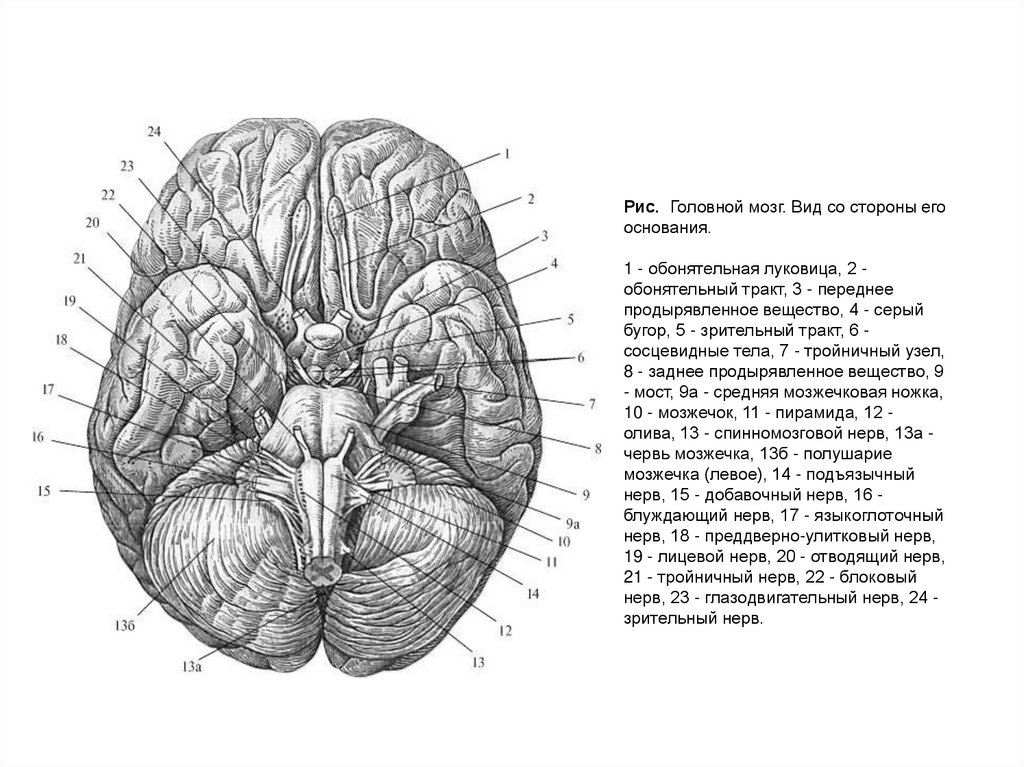

Необычные объекты: Переднее продырявленное вещество